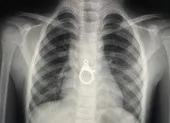

Ê kíp phẫu thuật gồm nhiều khoa phối hợp cứu bệnh nhân. Ảnh: Bệnh viện cung cấp

Cuộc phẫu thuật kéo dài 5 giờ 30 phút, êkíp gồm 4 khoa phối hợp phẫu thuật, khâu lại động mạch chủ ngực đoạn xuống, khâu thực quản ngực, cô lập thực quản ngực và động mạch chủ ngực bằng mở màng tim kết hợp nội soi thực quản trong lúc mổ để xác định lại vị trí lỗ rò đã được khâu kín, đồng thời mở dạ dày ra da nuôi ăn.